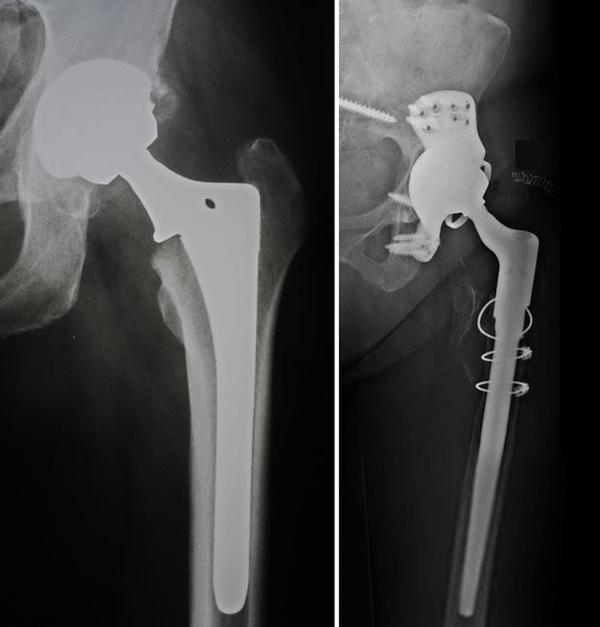

Sports injuries or accidents can damage crucial knee ligaments like the ACL, PCL, or PLC. At SHIVAM ADVANCED ORTHO CARE Bangalore, knee ligament reconstruction helps restore stability, strength, and confidence in movement. The procedure involves replacing the torn ligament with a graft, usually from the patient's own tissue, to reestablish knee function. Advanced arthroscopic techniques allow minimal incisions, faster recovery, and reduced pain. Patients regain better control, improved balance, and greater mobility after rehabilitation. The expert surgeon DR.AMARDEEP at SHIVAM ADVANCED ORTHO CARE design personalized recovery plans that include physiotherapy and muscle-strengthening exercises. This ensures full range of motion and lasting results. Whether you are an athlete or someone dealing with accidental ligament damage, this treatment offers a path back to active living. To regain joint stability and confidence, contact SHIVAM ADVANCED ORTHO CARE Bangalore for specialized knee ligament reconstruction.